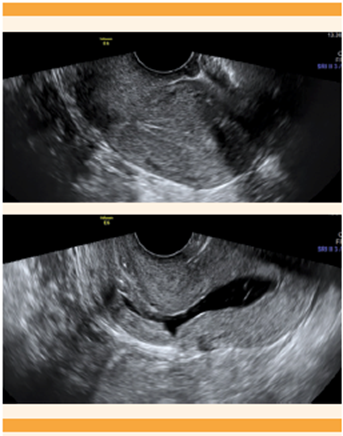

La ecografía transvaginal es la modalidad de imagen diagnóstica de elección para la detección de pólipos endometriales (Figura 5). Su precisión aumenta cuando se utiliza Doppler color o se practica una ecografía con infusión de solución salina (histerosonografía).20,21 Es importante tener en cuenta el endometrio de aspecto polipoide, que se considera una variante normal. 12

Está demostrado que la ecografía transvaginal tiene una sensibilidad y especificidad similares para diagnosticar adenomiosis cuando se compara con la resonancia magnética nuclear. 1,26 En la actualidad, para el diagnóstico de adenomiosis se utilizan los criterios del grupo MUSA, 27 en donde dos o más criterios son por demás sugerentes de adenomiosis. Los criterios son: engrosamiento miometrial asimétrico, quistes miometriales, islas hiperecogénicas, sombreado en forma de abanico, líneas y brotes subendometriales ecogénicos, vascularización translesional, cuando haya una zona de unión irregular y una zona de unión endometrial interrumpida. A pesar de lo anterior, aún se está trabajando en un consenso internacional que pueda definir un sistema de clasificación de adenomiosis que permita fenotipar el trastorno de una manera estandarizada. 1 Figura 6